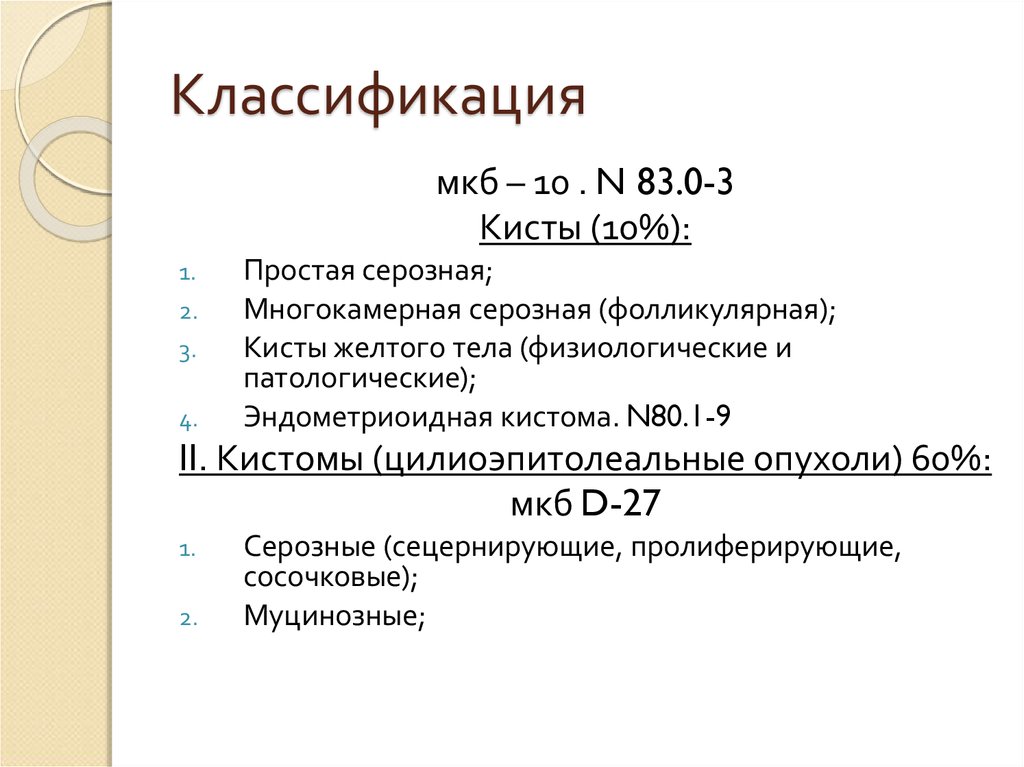

Код мкб 10 атерома головы

Код мкб 10 атерома головы 109 фото